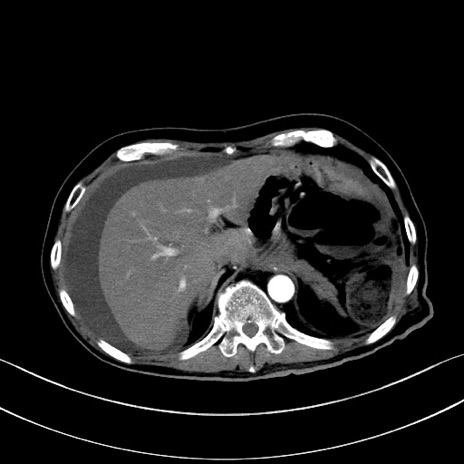

症例28(横断像)

【症例】60歳代男性

【現病歴】胃癌にて胃全摘後。食思不振が悪化し、夜中に嘔吐することがある。

【既往歴】胃癌、胃全摘、脾摘、胆摘後

【データ】WBC 5900、CRP 10.56